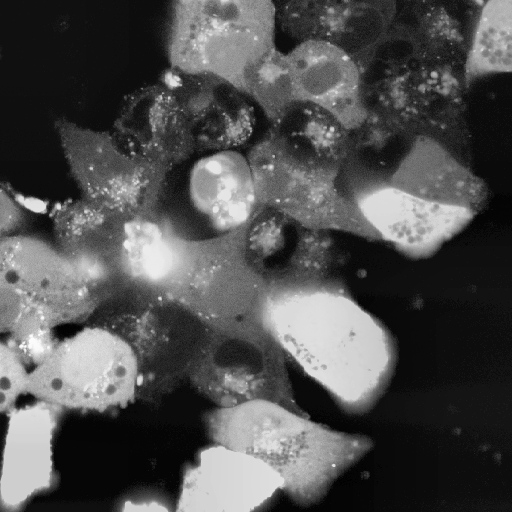

Highest quality images identified by the lowest PIQE, NIQE and BRISQUE scores were subjected to the expertise of an experimentalist researcher with extensive experience of working with signals from HL-1 networks, which empirically determined the existence of incongruencies between the perceived quality assigned by each NR-IQA score and the visual quality and usefulness of the image for GT annotation (see Section 6.2). Figure 4 reports the results of this analysis, comparing images identified of High Perceived Quality (HPQ) by PIQE, NIQE and BRISQUE scores (Figure 4a) with images considered to have better perceived quality by the expert. It is worth noticing that, while HPQ images identified by the experimentalist substantially outperform the quality of the best HPQ images identified by PIQE and BRISQUE, we found agreement between the HPQ images identified by NIQE and the ones chosen by the experimentalist, with three out of four images scoring similar NIQE scores to the HPQ images selected by the experimentalist. Oppositely, PIQE and BRISQUE showed incongruencies between the score assigned to the best (Figure 3a) and median quality images (Figure 3b) and the translation of these scores into the effective perceived quality of the images. Therefore, both scores assigned HPQ values to low brigthness images characterised by poor foreground-to-background contrast and extremely impaired visibility of regions of cellular density and most importantly of cellular boundaries, essential to allow the annotations of HL-1 images.

Amongst the six projection methods tested in the study, MIP, QP and SP methods were selected by the experimentalist as the methods yielding HPQ images (Figure 9). The preprocessing-projection combination methods selected were shown to generate images with high foreground-to-background contrast, which, together with high image brightness, facilitates the differentiation of cellular and background material in HL-1 images. These methods were also associated with an increased perceptive visibility and sharpness at cellular boundaries, making cell-to-cell connection more visible and facilitating the experimentalist in the recognition of cellular structures that characterise complex HL-1 networks for downstream GT annotation (as discussed in Section 6.2). Interestingly, CH and GH preprocessing methods in combination in two out of four of these methods, associated with MP and SP projections, and again in their lower value version (i.e., GL and CL) with SP projections and CL alone with QP methods (as shown in Figure 6). Notably, combined CH and GH approaches, preceded or followed by filtering methods, MB, NF and BF amongst the most common, also appear in the best methods combinations identified by PIQE, NIQE and BRISQE scores (see Figure 5). The value of using CLAHE with GF methods and NF techniques has been previously shown in medical imaging datasets [36], but never tested on FM datasets and in combination with projection methods for multi-temporal image fusion.